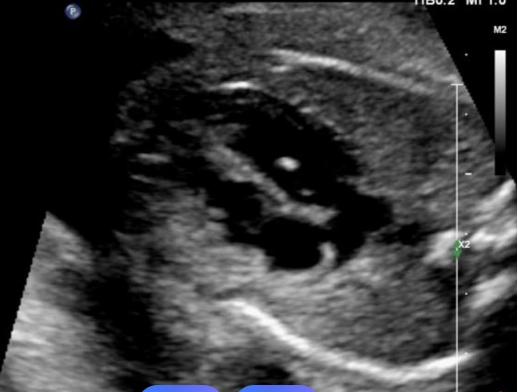

2. 心室强光点(EIF)

1)是什么?在胎儿心室内看到的像小亮点一样的回声,常见于左心室。

2)意味着什么?在唐氏综合征胎儿中出现率较高,但在亚洲人群的正常胎儿中也极其常见(尤其单独存在时)。它被认为可能与乳头肌腱索的炎性改变或钙化有关。

3)怎么办?如果仅仅是孤立性的心室强光点,而您的唐筛/NIPT风险低,且年龄不大,通常被认为没有明确的临床意义,只需定期观察即可。如果同时存在其他软指标或高危因素,则需进一步咨询。